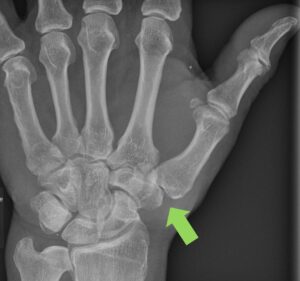

Postoperativ: Das Vieleckbein wurde entfernt, somit verbesserte Beweglichkeit am Daumen. Zusätzliche Sehnenaufhängung zur Stabilisierung des Daumens erfolgt.